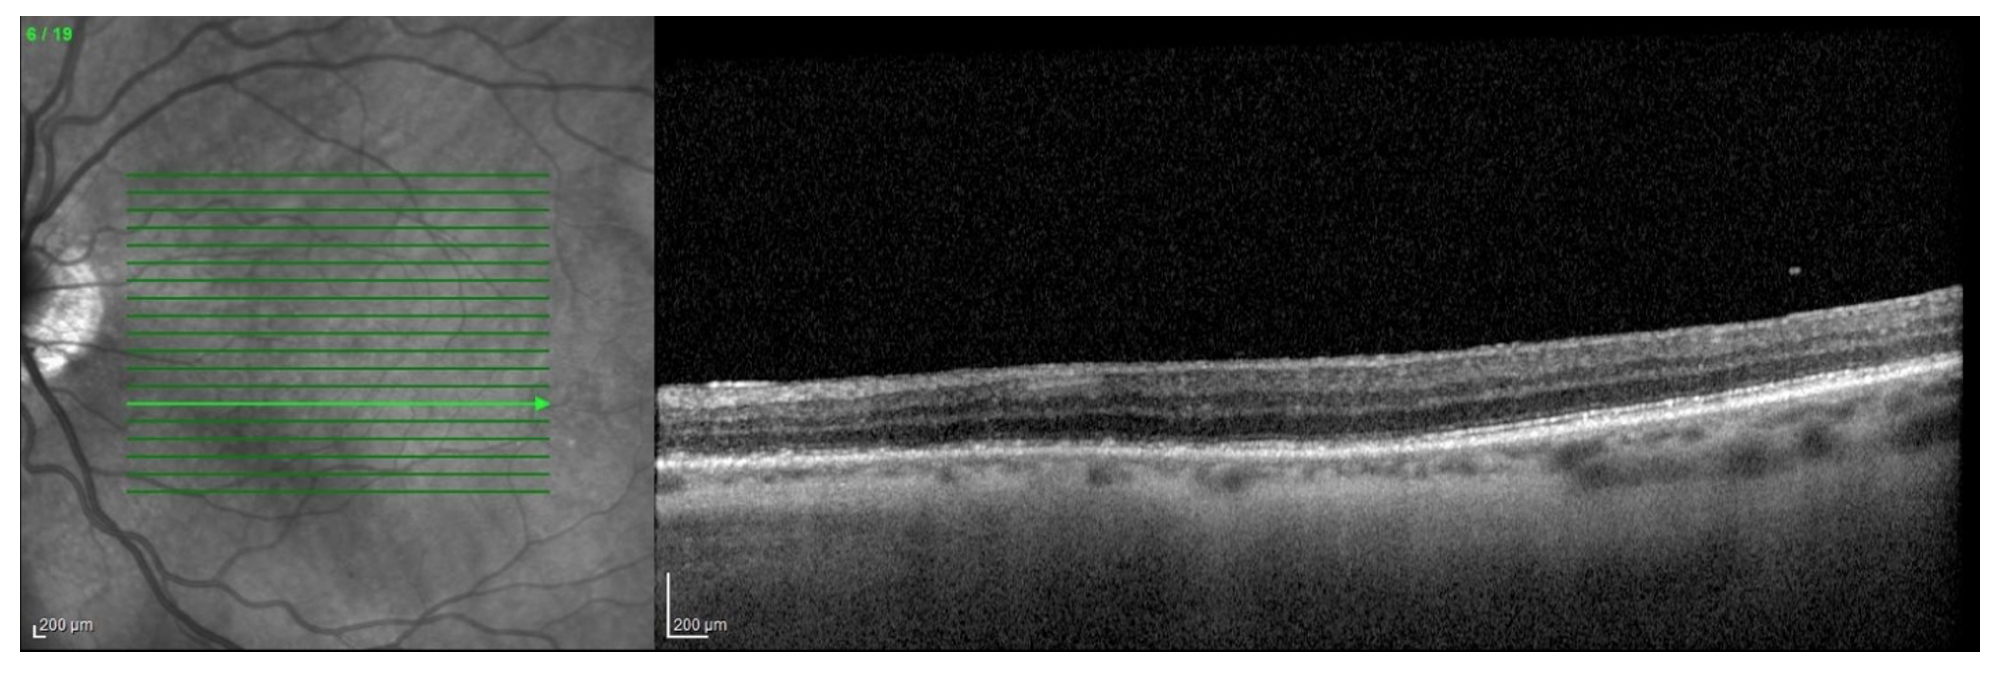

A 77-year-old female with history of cataracts, HTN, HLD, DM2, and aortic stenosis presents for new spots in the left eye. She denies flashes of light, photophobia and new floaters. Visual acuity is 20/40 OU (uncorrected) and anterior segment exam demonstrates trace nuclear sclerosis OU without vitreous cell in either eye. What is the diagnosis? What other diagnoses should be considered? How would you manage this patient?